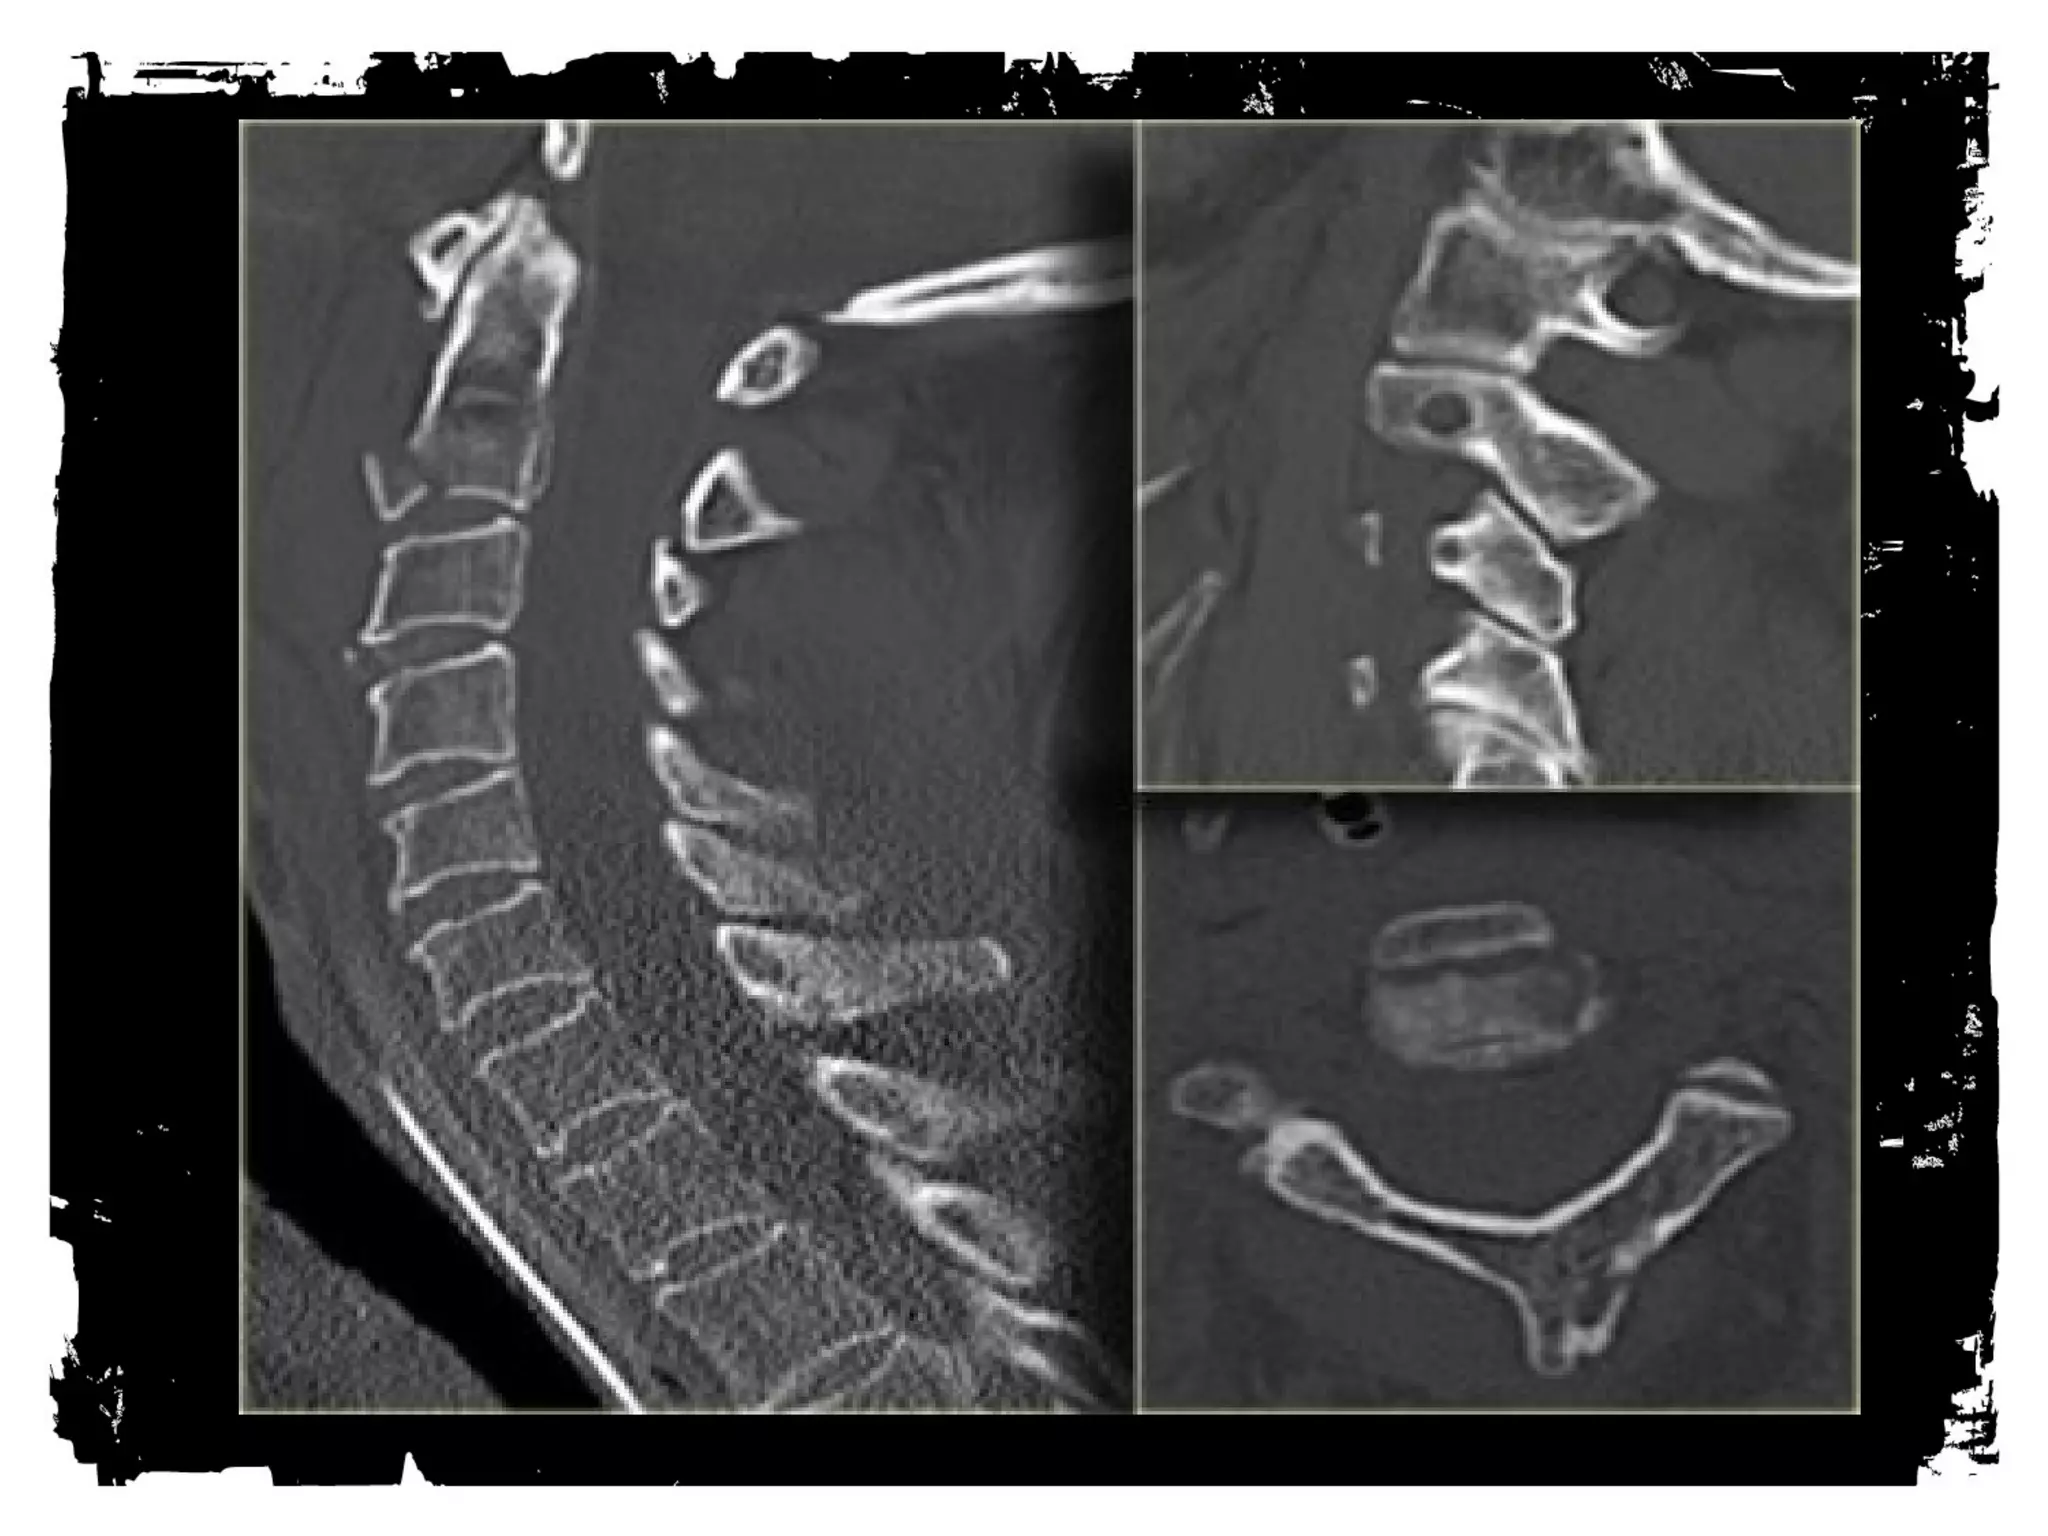

Case (8)

Jefferson Fracture

Burst fracture of ring of C1

Axial loading in the occiput

No associated neuro deficts ( C1 ring is wide!)

> 2mm dislocation of lateral masses of C1 or

odontoid view is diagnostic, 1-2 mm is equivocal

( rotation of head?)

Predental space > 3 mm: disruption of transverse

ligament

1/3 associated with C2 fracture